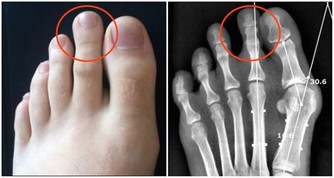

① 肝臟受損。喝酒過度,容易使脂肪堆積在肝臟,損傷肝細胞,甚至誘發脂肪肝。